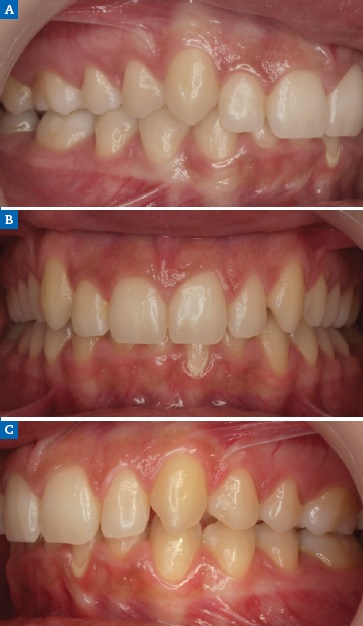

A 19-year-old female patient presented with primarily esthetic concerns. An intraoral examination revealed a Class I right molar, a Class II left molar, and a deep bite (Figure 17). Orthodontic treatment was performed to obtain bilateral Class I molar and canine relationship and, in turn, improve the overbite and remove the traumatic occlusion responsible for the gingival recession on the left mandibular incisor. Bolton’s anterior analysis confirmed a dental discrepancy in the anterior sector to mandibular excess with a proportion of 83.1% (13, 12, 11, 21, 22, 23 / 43, 42, 41, 31, 32, 33). It was caused by the maxillary dental microdontia and the need to carry out esthetic restorations in the upper arch. A space was created on the distal surface of both microdontic lateral incisors to establish the Bolton’s proportion17 (Figure 18). After orthodontic treatment, shade selection was accomplished using a Vita Shade Guide (Figure 19), and dental bleaching was performed to optimize the harmony of the smile.

Figure 17 Case 3: Initial intraoral views of the (A) right, (B) frontal, and (C) left aspects before the orthodontic treatment, revealing a Class I right molar, a Class II left molar, and a deep bite.

Figure 18 Case 3: Intraoral views of the (A) right, (B) frontal, and (C) left aspects after the orthodontic treatment.